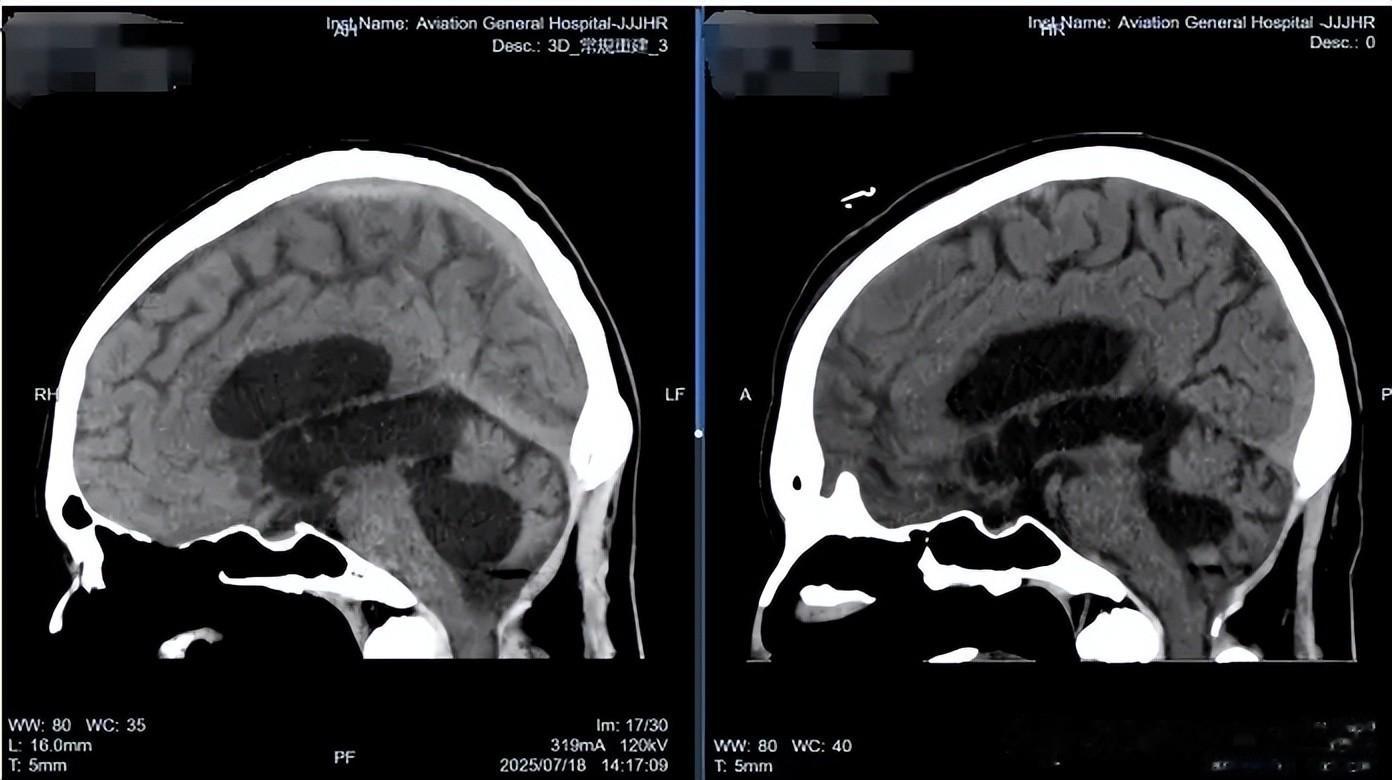

软性神经内镜术前术后对比

术后,王先生的脑脊液 NGS 检验提示大肠埃希菌感染,肖庆教授团队迅速调整抗炎治疗方案,同时密切监测脑脊液情况,逐步抬高、关闭外引流。在医护人员的精心照料下,王先生的病情稳步好转,头晕、头痛症状完全消失,四肢活动自如,未遗留任何神经功能缺损。复查CT显示脑室系统较前缩小,脑脊液循环恢复稳定。随后,肖庆教授团队成功为王先生行脑室分流管去除术,历经31天的精心治疗与康复,王先生终于摆脱了牵制他大半生的分流管。